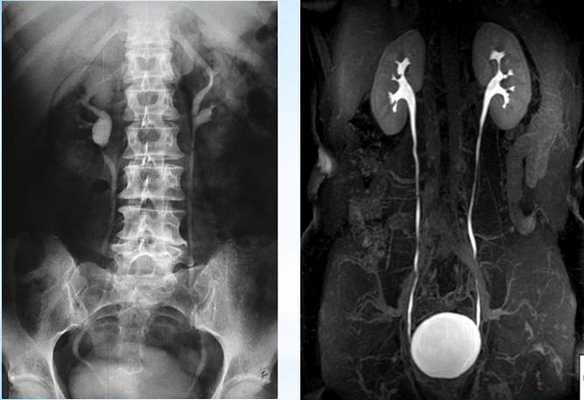

Диагноз стриктуры мочеточника устанавливает врач-уролог по результатам УЗИ почек, УЗДГ сосудов, рентгеноконтрастного обследования, КТ почек и МРТ. Проведение трехмерной УЗ-ангиографии с диуретической нагрузкой позволяет одновременно увидеть расширенный отдел мочеточника выше стриктуры и оценить сосуды почек.

Рентгенконтрастная урография (экскреторная, инфузионная, ретроградная) дает возможность визуализировать ткани почек и мочевыводящие пути, определить сужение мочеточников, протяженность стриктур, оценить снижение выделительной способности почек. В сложных случаях применяют КТ или МРТ, дополнительно выявляющие заболевания смежных органов и тканей, оказывающих влияние на почки и мочеточники.

КТ-урография. Резкое расширение чашечек и лоханки левой почки (красная стрелка), отсутствие контрастирования суженного левого мочеточника (синяя стрелка).